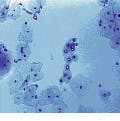

An important medical application of optical-correlator technology is in the area of automated screening of cervical-smear slides. Typically, each slide is screened at 20X, and 3600 images measuring 400 ¥ 400 mm are processed. To automate this procedure, researchers Ramkumar Narayanswamy, John Metz, Rosemary Stewart, and Kristina Johnson of the Optoelectronic Computing Systems Center of the University of Colorado (Boulder, CO) are developing an optoelectronic automated two-step screening system.

In the first processing step, the slide is examined at high speed (up to 1000 images per second) to locate and mark suspicious regions. "This region-of-interest (ROI) detection reduces the amount of data requiring computer classification by a factor of 1000," says Metz. The classification system looks at various features of the nuclei, such as texture of the nucleoplasm and fractal dimension of the nuclear membrane, using traditional image-processing techniques on a PC. Because the PC classification step takes a long time for large data sets, data reduction without loss of important information becomes essential.

"Our optical/electronic ROI detector provides this high-speed data reduction without eliminating the crucial pieces of information necessary for diagnosis. Thus, most of the "hay" in the "needle-in-a-haystack" problem has been removed, making finding the needle much easier," says Metz. The ROI detection is performed using mathematical morphology feature detection in the form of a hit/miss transform (HMT) to detect the shape and size of the cell nucleus. If the nucleus is circular with a diameter larger than 10 µm and smaller than 20 mm, the cell is identified as suspicious. "This eliminates unwanted areas of the slide such as white blood cells and larger items such as air bubbles and dust particles," says Metz.

Computer simulation of the algorithm tested on 184 Pap-smear images detected 95% of the suspect regions as suspect, while tagging just 5% of the normal regions as suspect (see Fig. 5). The HMT transform is currently being performed optoelectronically using an optical correlator. This morphological processor uses an optically addressed SLM for image acquisition with a laboratory microscope; it also performs incoherent-to-coherent optical conversion. A 256 ¥ 256 electrically addressed SLM operating in the phase mode at the filter plane and a custom-designed smart-pixel VLSI integrated circuit at the output plane perform fast detection and calculation of the HMT output.

FIGURE 5. A typical cervical-smear image shows a region of abnormal cells in the center of the image with normal cells on both sides and across the entire bottom of the image (top). Abnormal cells are distinguished by their larger nuclei and lower nuclear cytoplasm ratio (bottom). A computer simulation of the hit/miss transform tested on 184 Pap-smear images detected 95% of the suspect regions as suspect while tagging just 5% of the normal regions as suspect.